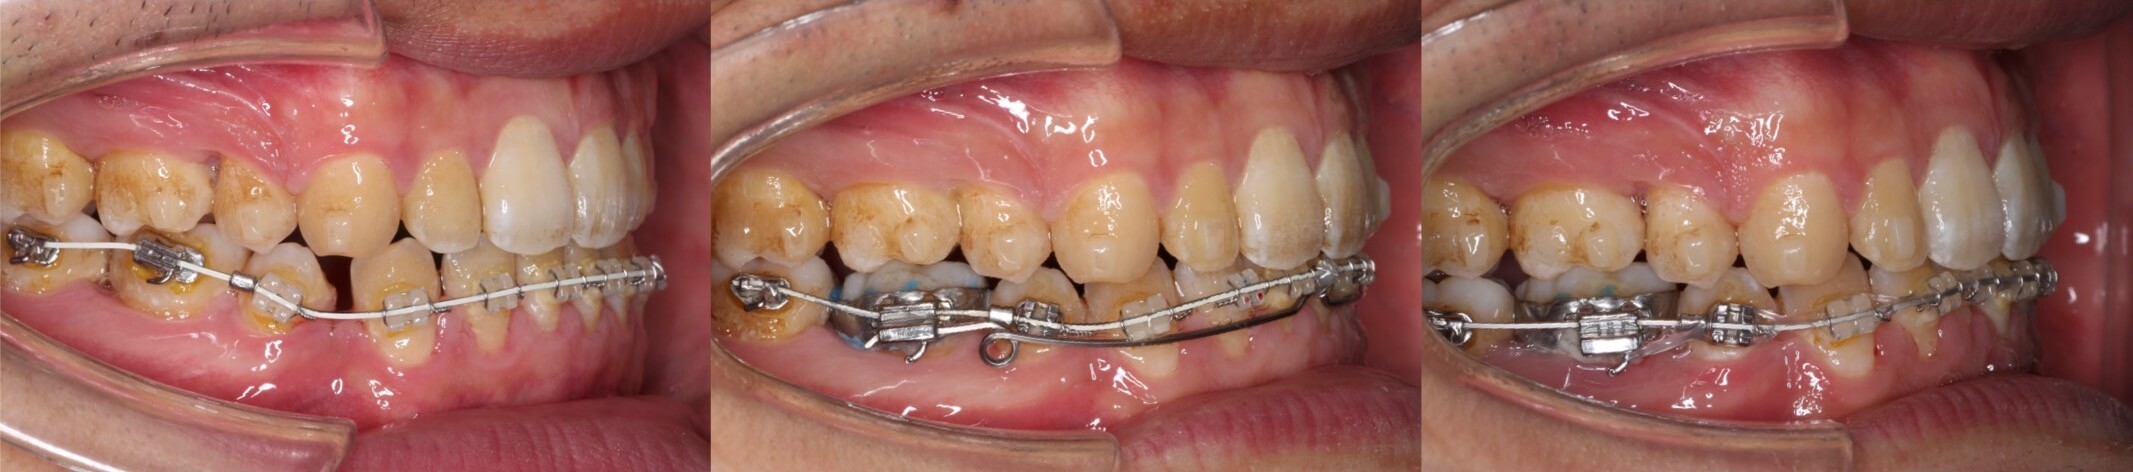

実際にマウスピース型矯正治療でボーイングエフェクトが発生したケースです。抜歯空隙に隣接歯が倒れ込み、前歯部では過蓋咬合、臼歯部では離開が起きています。

マウスピース型矯正装置のみでのリカバリーは困難と判断し、重度の臼歯傾斜が発生している下の歯列のみ唇側矯正装置でリカバリーを行いました。途中ワイヤーを2本使用することで、歯にモーメントを発生させ、無事ボーイングエフェクトが解消しました。リカバリーにかかった治療期間1年3か月と長期にわたりました。

<ボーイングエフェクトのメカニズム>

<ボーイングエフェクトのリカバリー>